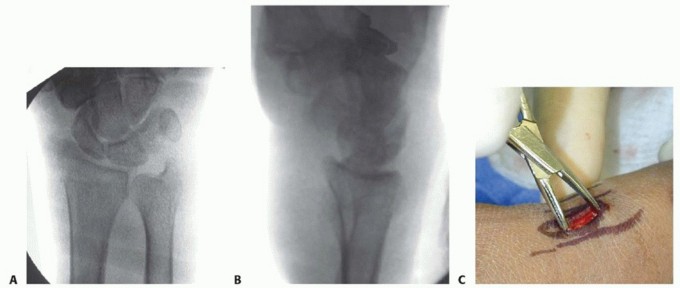

NONBRIDGING EXTERNAL FIXATOR APPLICATION

TECH FIG 6 • A. Distal pin placement. B. Final reduction with nonbridged external fixator in place. This pin should be placed parallel to the first pin in both planes, with the starting point halfway between the radiocarpal joint and the fracture.The two proximal radius pins are placed using the technique described for placement of a bridging external fixator.The incisions are closed, after which the clamps are applied but not tightened. Reduction is achieved by manipulation of the distal pins and clamps.Pushing the pins in the dorsal/volar plane corrects dorsal tilt. Adjusting the pin clamp can correct radial inclination.Reduction is confirmed using fluoroscopy, and the clamps are tightened ( TECH FIG 6B).P.260